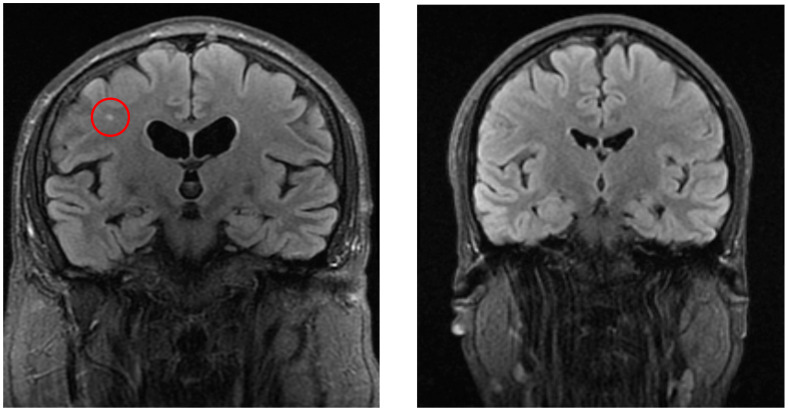

Background/Objectives: Dizziness is a frequent medical complaint with neurological, otolaryngological, and psychological origins. Imaging studies such as CT (Computer Tomography), cervical X-rays, and ultrasound aid diagnosis, while MRI (Magnetic Resonance Imaging) is crucial for detecting brain abnormalities. Our purpose is to identify structural brain changes associated with vertigo, assess pre-MRI diagnostic approaches, and evaluate treatment strategies. Methods: A case-control study of 232 vertigo patients and 232 controls analyzed MRI findings, pre-MRI examinations, symptoms, and treatments. Statistical comparisons were performed using chi-square and t-tests (p < 0.05). Results: White matter lesions, lacunar infarcts, Circle of Willis variations, and sinusitis were significantly more frequent in vertigo patients (p < 0.05). Pre-MRI diagnostics frequently identified atherosclerosis (ultrasound) and spondylosis (X-ray). Common symptoms included headache, imbalance, and visual disturbances. The most frequent post-MRI diagnosis was Benign Paroxysmal Positional Vertigo (BPPV). Treatments included lifestyle modifications, physical therapy (e.g., Epley maneuver), and pharmacological therapies such as betahistine. Conclusions: MRI revealed structural brain changes linked to vertigo. Pre-MRI assessments are essential for ruling out vascular and musculoskeletal causes. A multidisciplinary treatment approach is recommended. Trial Registration: This study was registered in ClinicalTrials.gov with the trial registration number NCT06848712 on 22 February 2025.

Abstract Image